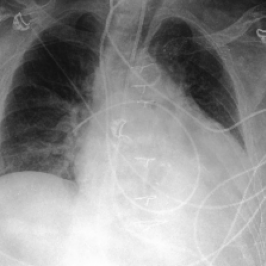

Waterbirds (Sagawa et al., 2020) is an image classification dataset where bird types are associated with a spurious background attribute (water or land). CelebA (Liu et al., 2015) is an image classification dataset, where hair color is an imbalanced attribute with respect to gender. MultiNLI (Williams et al., 2018) is a text benchmark of categorizing two sentences as entailing each other, contradicting each other, or neutral. The spurious correlation is between negation words like “never” and the “contradiction” label. CivilComments (Borkan et al., 2019) is a toxicity text classification dataset containing underrepresented demographic groups. CheXpert (Irvin et al., 2019) is a large-scale medical dataset of chest radiographs with rare pathologies, especially amongst certain minority groups.